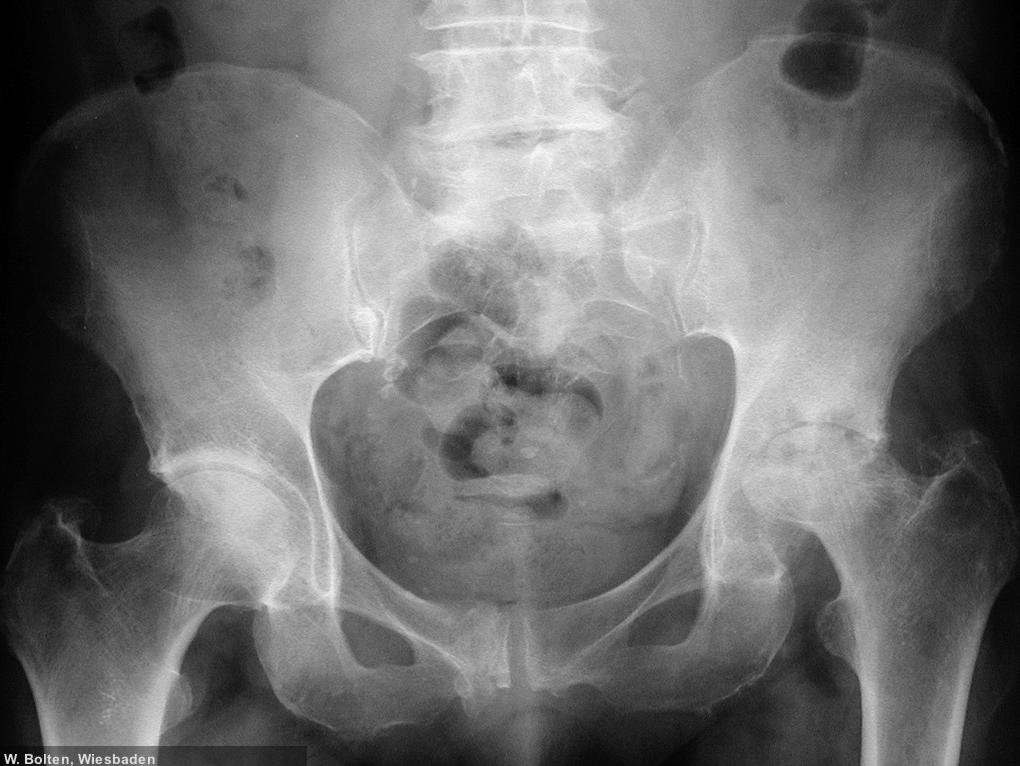

|  Dr. Wolfgang W. Bolten, Wiesbaden

Hüftkopfnekrose links, Coxarthrose rechts